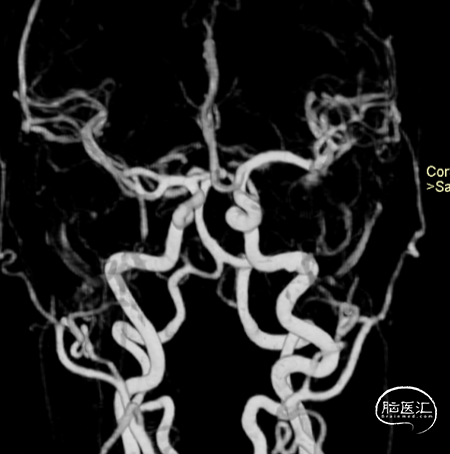

术后6个月造影随访提示动脉瘤完全愈合,载瘤动脉通畅。

4、该病例即刻造影显示血流重构满意,瘤腔内血流明显淤滞。术后六个月及12个月随访,均显示动脉瘤愈合,载瘤动脉通畅无狭窄。